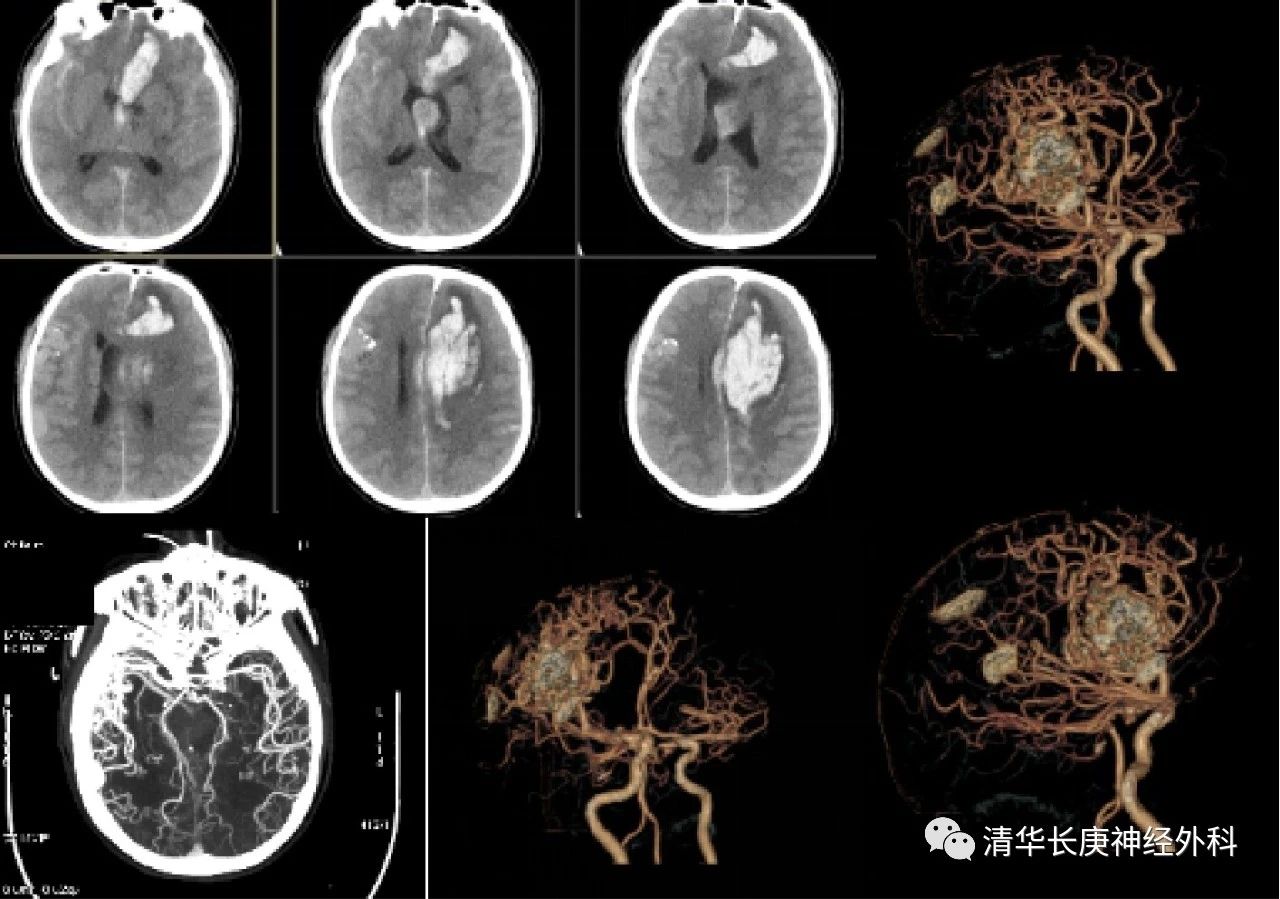

67岁的刘先生,5小时前出现意识障碍伴右侧肢体无力,家属联系救护车送至我院急诊,转运期间,患者出现意识逐渐下降至深昏迷,呼之不应,脑血管CT成像提示“脑出血,脑血管畸形,可疑左侧大脑前动脉动脉瘤”。患者手术风险极大,但已经出现脑疝,生命危在旦夕,刻不容缓,遂紧急行开颅手术。

图1 术前头颅CT及CTA,脑内血肿伴血管畸形

手术中行显微镜下脑内血肿清除,探查发现患者左侧大脑前动脉瘤破裂,考虑为本次脑出血的致病根源,予手术夹闭,探查发现右侧后交通动脉瘤,同时行手术夹闭,消灭了以后患者此处动脉瘤破裂出血的危险。这种类型的患者病情极其凶险,出血量大,治疗极其困难,若不及时手术治疗,很难存活。